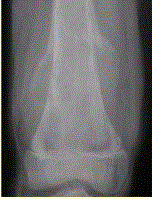

问题 患者男,16岁,左大腿下部疼痛伴肿胀2个月,逐渐加重。自感左膝上方胀痛,尤以夜间为著,伴行走困难。既往史及家族史无特殊。查体:左大腿下部明显肿胀,皮温较对侧升高。碱性磷酸酶明显增高。股骨平片及MRI见下图。 你认为对定性诊断有价值的征象是

选项 A.病变边缘模糊,内部信号不均 B.病变边缘骨皮质完整 C.病变周围可见软组织肿块 D.病变边缘可见骨膜反应,Codman三角形成 E.MR示病变周围骨髓明显水肿 F.病变内未见钙化影

答案 ACDEF